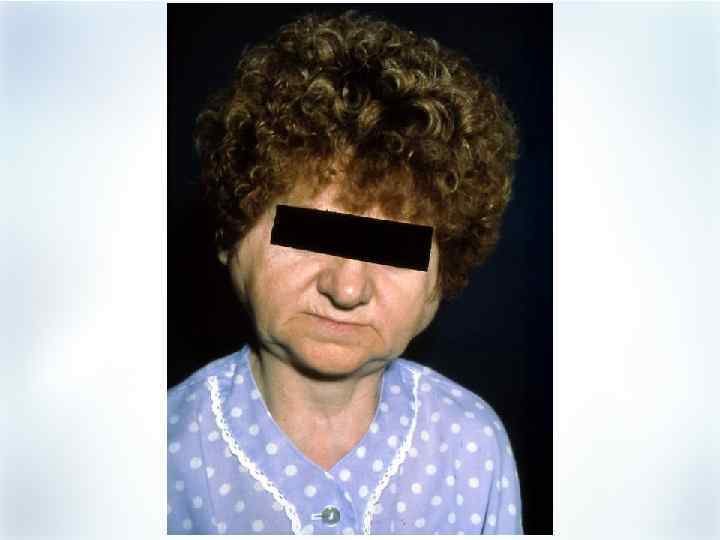

Поражение глаз при РА (редко) § § § Эписклерит Ирит Кератоконьюнктивит (при синдроме Шегрена) Осложнение – склеромаляция, прободение роговицы, энуклеация

Поражение глаз при РА (редко) § § § Эписклерит Ирит Кератоконьюнктивит (при синдроме Шегрена) Осложнение – склеромаляция, прободение роговицы, энуклеация

Ревматоидные узелки в области глаз Эписклерит при РА

Ревматоидные узелки в области глаз Эписклерит при РА